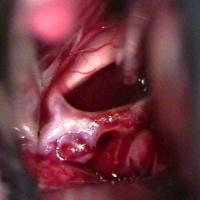

Aneurysma Hirntumor Bandscheibenvorfall

Aufgabe der Neurochirurgie ist die operative Behandlung der somatischen Erkrankungen des Zentralnervensystems und seiner Hüllen. Von Neurochirurgen werden Operationen an Gehirn, Rückenmark, peripheren Nerven sowie Schädel und Wirbelsäule durchgeführt. Solche Eingriffe sind unter anderem erforderlich bei allen Arten von Tumorerkrankungen, Unfallfolgen oder angeborenen Fehlbildungen von Gehirn und Rückenmark. Auch entzündliche Erkrankungen des Zentralnervensystems und spontan auftretende Blutungen infolge von Gefäßmissbildungen (Aneurysmen, Angiome) oder Schlaganfällen gehören zum Aufgabengebiet der Neurochirurgie. Ein weiterer Schwerpunkt ist die Behandlung degenerativer und traumatischer Wirbelsäulenprozesse, hier in erster Linie die Operation von Bandscheibenvorfällen sowie die operative Versorgung von Verletzungen der Wirbelsäule und des Rückenmarks. Nicht zuletzt werden auch Schmerzpatienten (z. B. bei Tumorerkrankungen, Trigeminusneuralgie, usw.) behandelt.